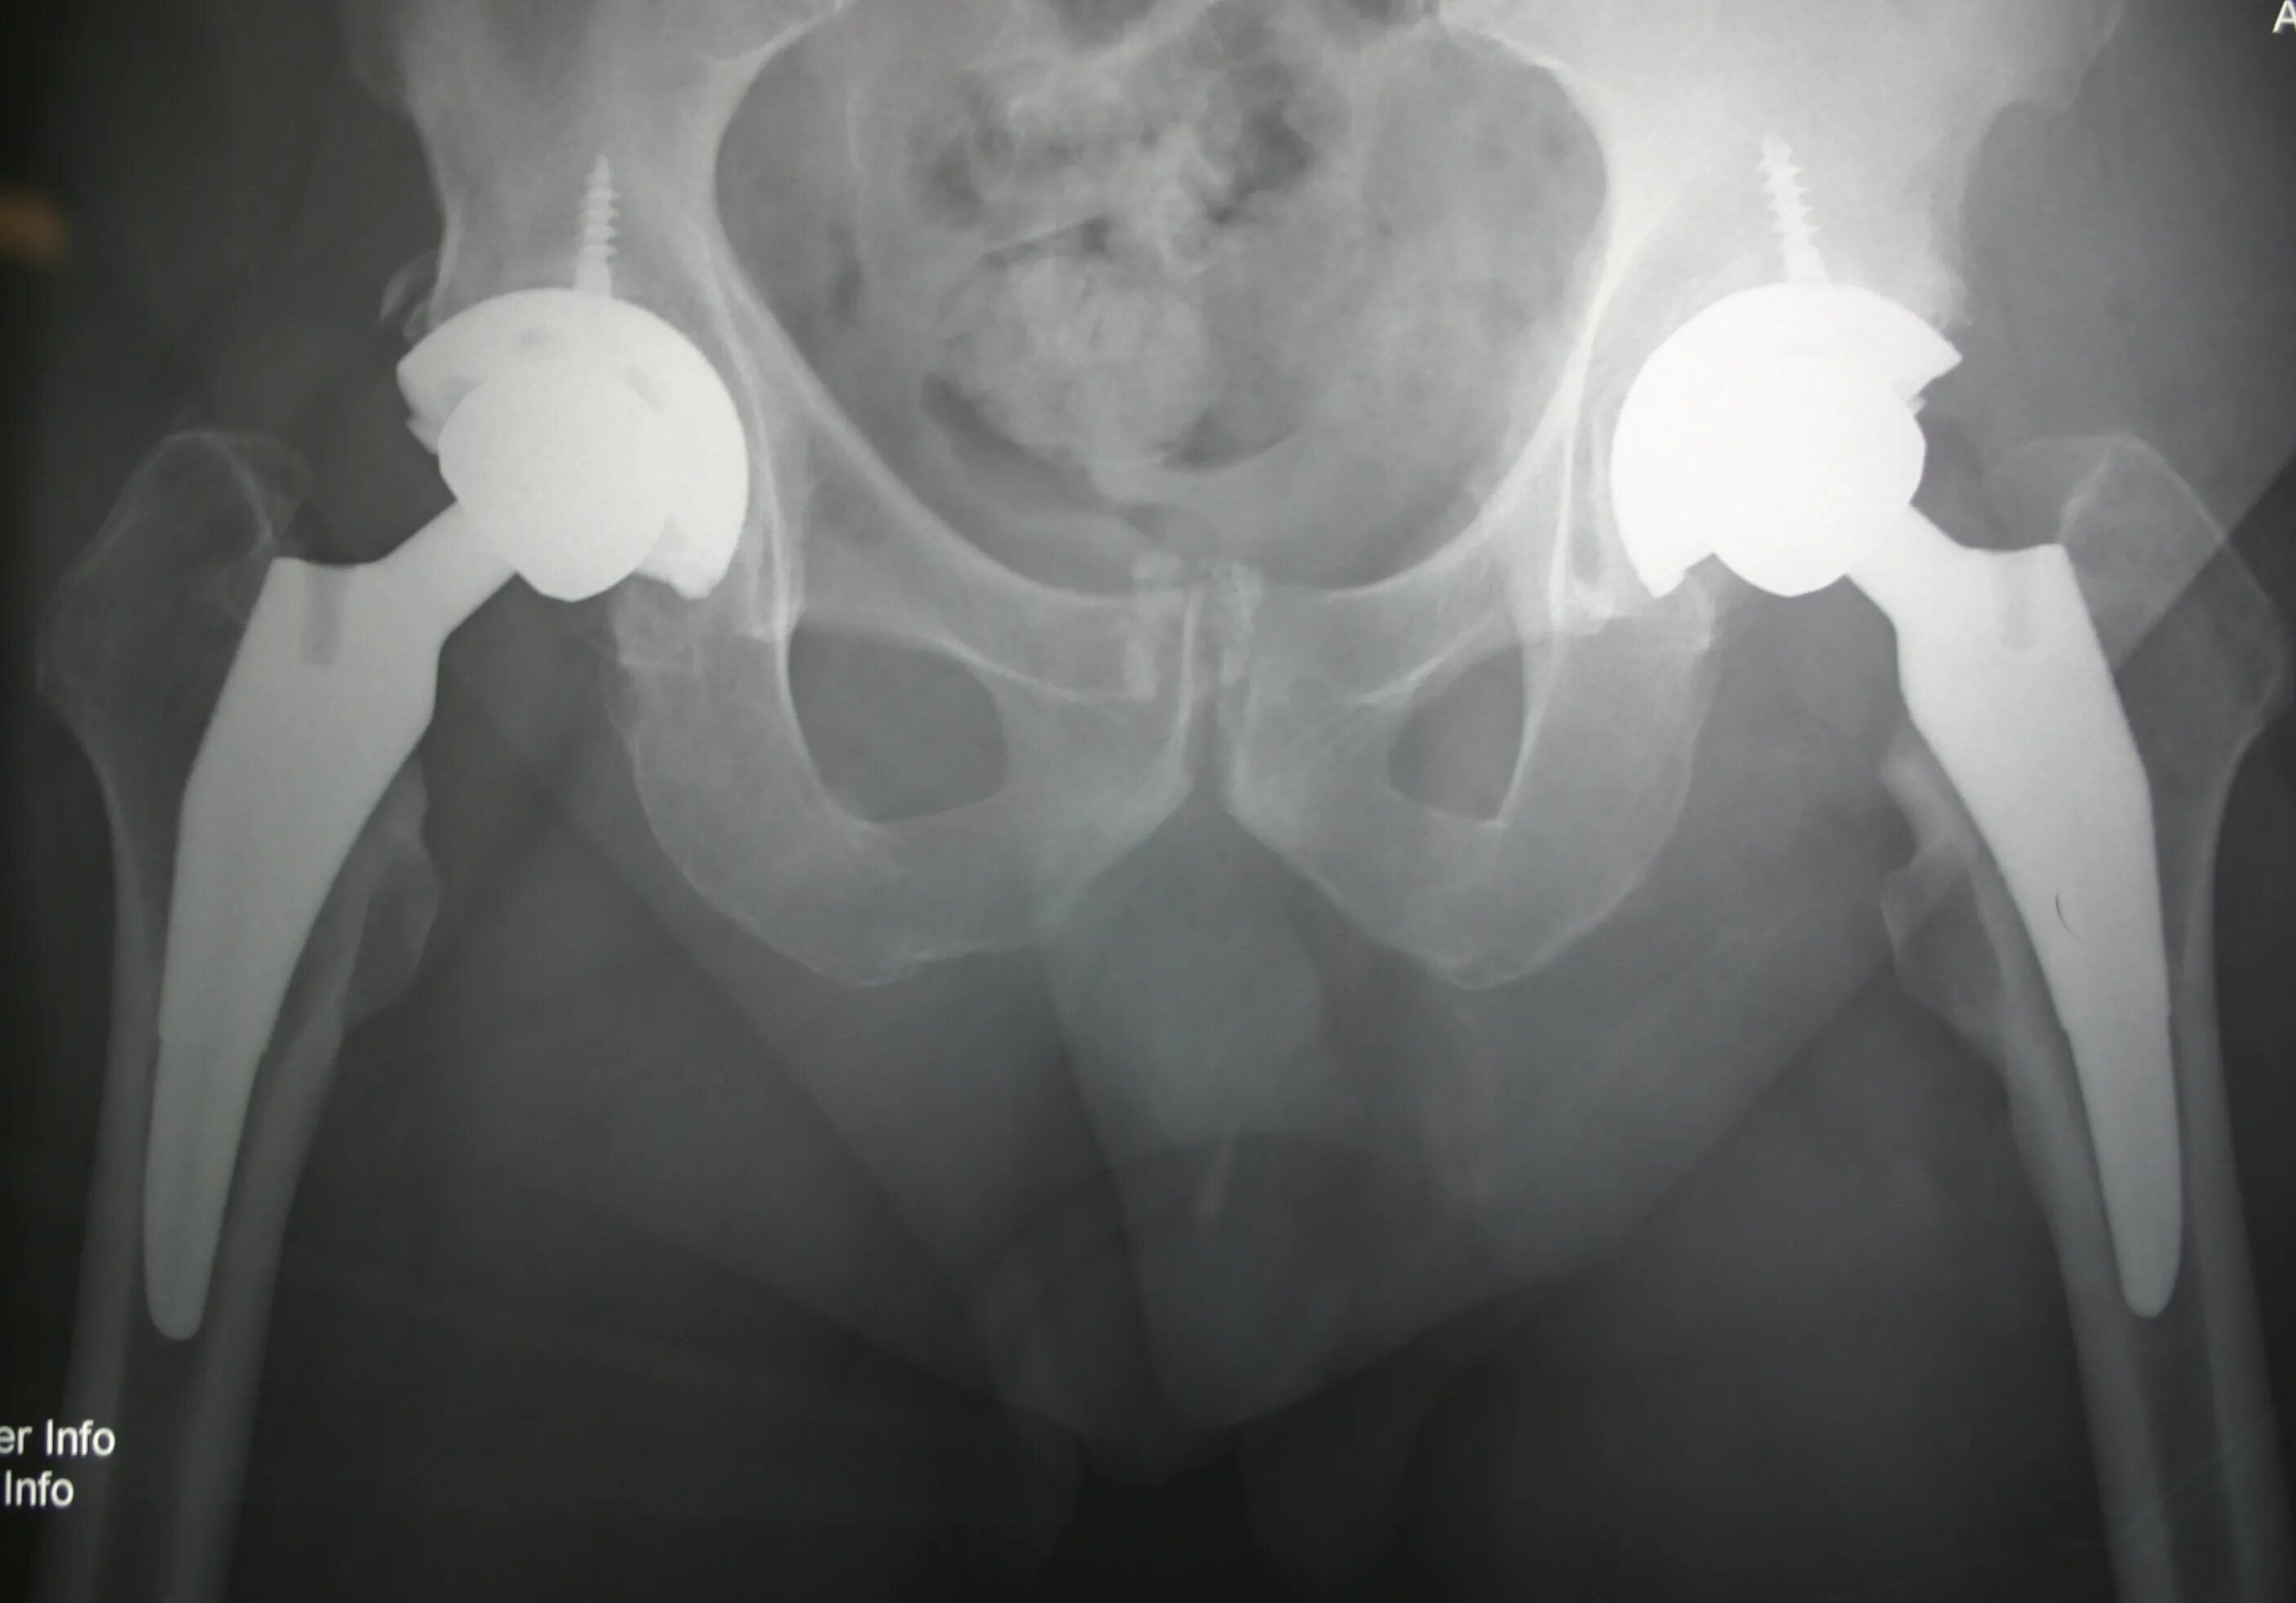

Эндопротезирование тазобедренного сустава центр